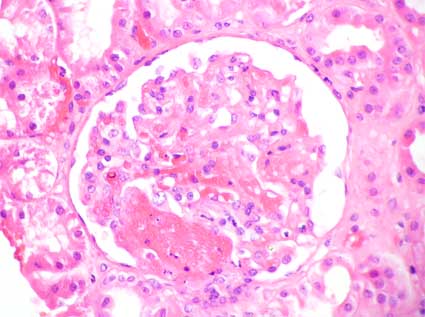

Figura 2.

H&E, X400.